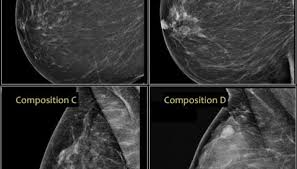

What Does Breast Cancer Look Like Pictures - Woman Shares Photo Of Her Breast To Show What Cancer Symptoms Look Like The Independent The Independent / The american cancer society couldn't do what we do without the support of our partners.. Brest) cancer is a common cancer among women. Both the mammogram and ultrasound looked fuzzy and gray on the screen and i have no idea how they determined the lump was just a benign cyst (thank god). People who are over 40. There's been a lot of press about not needing to do self breast exams, but i really do think it's important to have self awareness about how things might change in the appearance of your. One of the most common malignancies in women in the us cancer that starts in the breast.

Pictures and description of what does breast cancer look like on mammogram for 5 categories. Brest) cancer is a common cancer among women. One type of breast cancer, inflammatory breast cancer, does not usually cause a lump but instead in contrast to breast cancer tumors, benign lumps are often squishy or feel like a soft rubber ball with when looking at mammogram pictures, cancers often appear bright and the area around the. If the diagnosis is delayed, the cancer can spread to distant sites. Instead, breast skin can become thick, red, and look pitted, like an orange peel.

Without having seen a picture randomly with real information, i wouldn't have known what to look for, erin posted. Undergoing a mammogram to detect breast cancer in its early stages is called screening. Ibc doesn't look like a typical breast cancer. What is invasive breast cancer versus noninvasive breast cancer? It often does not cause a breast lump, and it might not show up on a mammogram. Sometimes, these spots have a raised border with an indentation in the center, according. Breast cancer lumps are usually hard and irregularly shaped. The 15 worst things you can say to someone with breast cancer. This is one of the many reasons it's important to know what is normal for your body. But remember, if breast cancer is caught while still 'in situ' (not yet penetrating the breast duct walls) there is very little risk of anything really bad happening. Not feel, but look like. I was diagnosed with breast cancer 5 days later and with stage 4 the following month. If the diagnosis is delayed, the cancer can spread to distant sites.